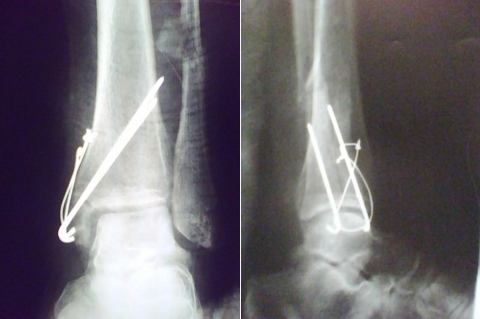

Fratura do Tornozelo - 2a Cirurgia

Paciente foi então submetido à nova cirurgia em nosso Serviço, tendo-se optado por fixação do maléolo medial pelo princípio de banda de tensão ( 2 FK e Fio de Cerclagem) com enxertia de tíbia proximal homolateral. Não realizada osteotomia da fíbula, então consolidada e algo encurtada.

Angulo talocrural pós-cirúrgico dentro dos padrões normais (8-15°), porém com 4mm de discrepância em relação ao lado contra-lateral.

Trata-se provavelmente de uma fratura tipo C de Weber e Supinação Rotação externa pela classificação Lauge-Hansenm que corresponde a aproximadamente 70% das fraturas do tornozelo do adulto. Não foi citado no caso a realização intra-operatória dos testes de estresse para sindesmose, de forma que, provavelmente, há lesão da sindesmose pelo traço de fratura. Minha conduta seria: 1) Iniciar síntese pela fíbula para ganho de comprimento e restabelecimento do angulo talo-crural; 2) Síntese do maléolo medial utilizando compressão inter-fragmentária com parafusos corticais de 3.5mm. Pelas imagens imagino que os fios K são de diâmetro 2.5mm e acredito que o risco de exposição dos fios (pelo trauma, repetidas abordagens e fio saliente na pele) é bastante elevado. Como disse, teria optado por síntese com parafusos.

Trata-se de uma fratura AO 44-C2,inicialmente deve ser tratada pelo principio da estabilidade absoluta, com osteossintese do maleolo medial e lateral, utilizando 02 parafusos de esponjosa 3,5 mm no medial e placa 1/3 tubular na fibula;Se temos principios, escolhemos nossos proprios metodos; com 50 dias de fratura,estamos tratando uma complicaçao de fratura,o tirante de tensão é uma opção no maleolo medial e a fibula não devem ter fixado pois devia está consolidada